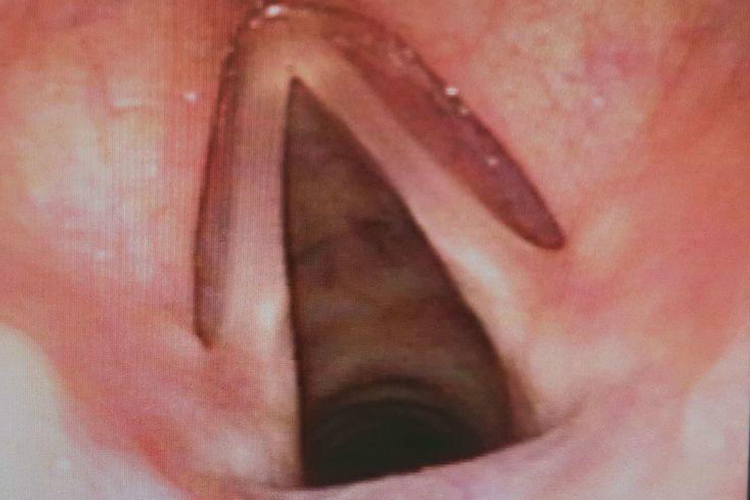

小孩正常喉咙是由喉软骨、韧带、纤维膜、喉肌和喉黏膜等共同构成的管腔。喉腔上起自喉口,与咽相通,向下经气管通支气管和肺。喉腔侧壁有上、下两对黏膜皱襞,上方的一对称前庭襞,下方的一对称声襞。上述两对皱襞将喉腔分为3部分,即前庭襞上方的喉前庭、声襞下方的声门下腔、前庭襞和声襞之间的喉中间腔。

喉咙发炎一般是喉炎,如行间接喉镜检查,可见喉部黏膜充血、肿胀。声带由白色变为粉红色或红色,有时可见黏脓性分泌物附着。声门下黏膜因肿胀而向中间隆起。会出现声嘶、咳嗽、呼吸困难等症状。